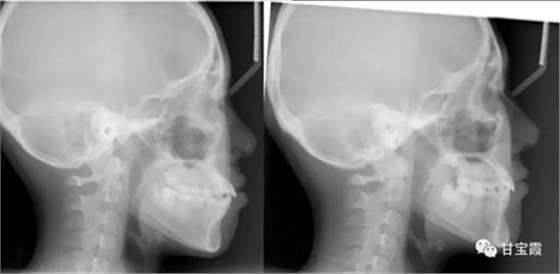

下面這兩張X片子就是矯正前后的對比,看不出下頜缺牙

下面的矯正前后的對比照片看出側(cè)貌得到了改善